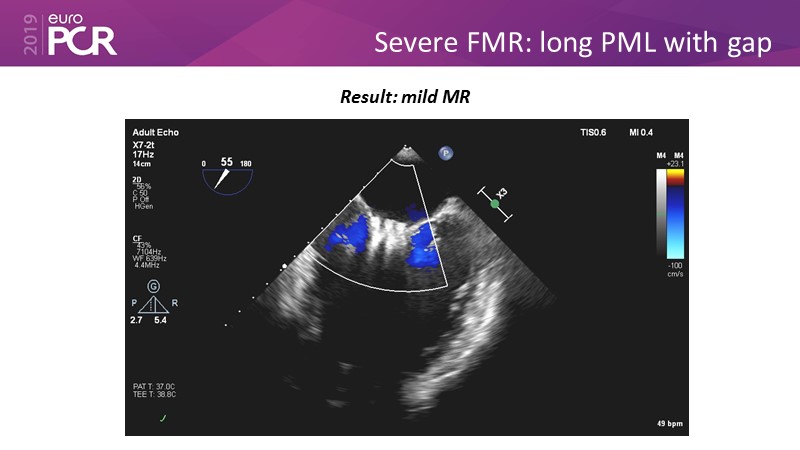

- To learn how will product innovation (Mitraclip NTR / XTR) drive improvement in procedural and clinical outcomes (EXPAND)